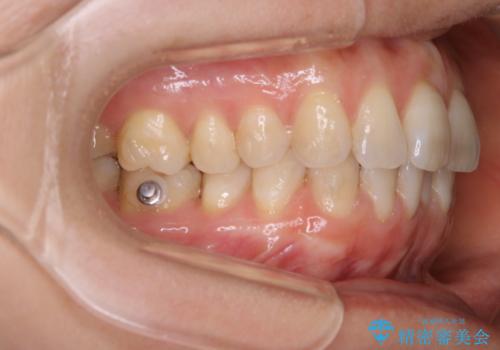

- インビザラインFULL

- 1年

インビザラインFULLで奥歯の噛み合わせから改善させることで、上下の真ん中位置をしっかり合わせることが出来ました。